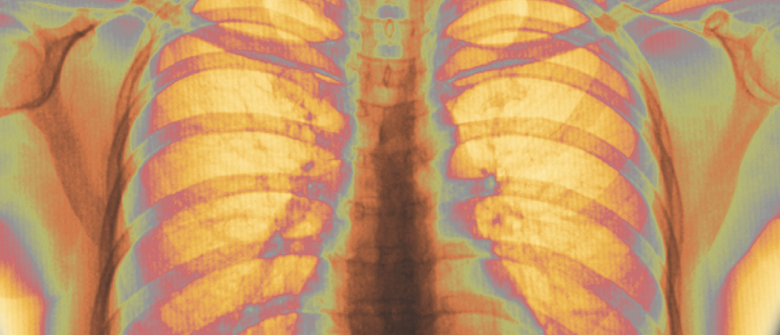

ACP Releases Best Practices for Evaluating Suspected Pulmonary Embolism

The American College of Physicians has issued new guidelines for the evaluation of patients with suspected acute pulmonary embolism (PE).

These guidelines come in response to rising rates of tests for suspected acute PE, and the potential harm associated with overuse of specific tests, including computed tomography and plasma D-dimer.